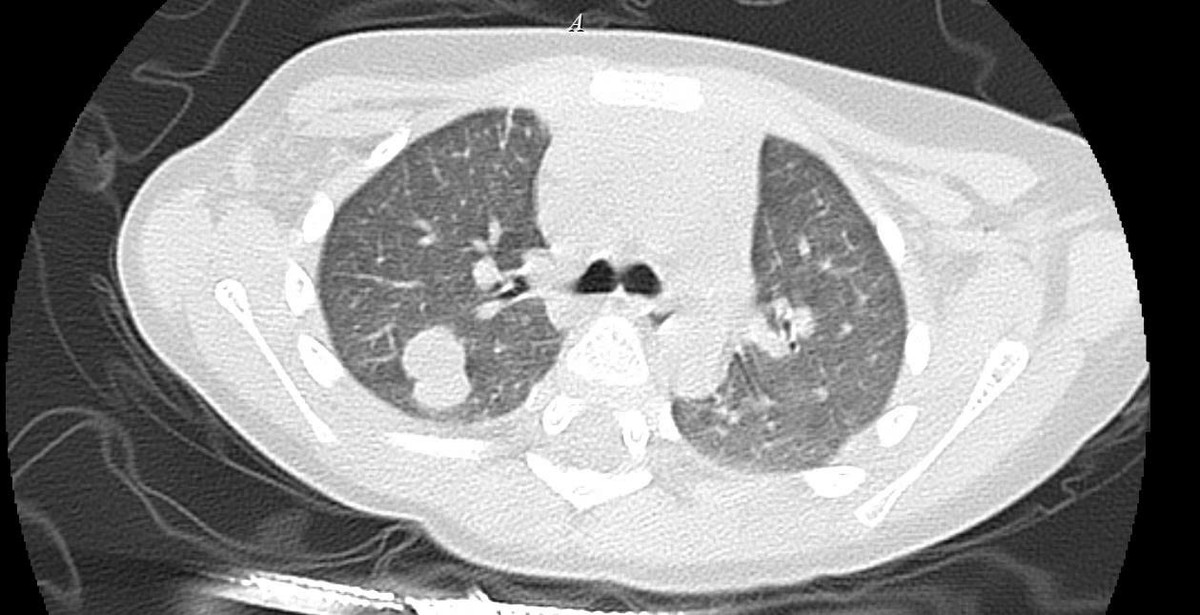

ut-tinh-hoan-1.jpg

Hình ảnh tổn thương di căn - Ảnh BVCC